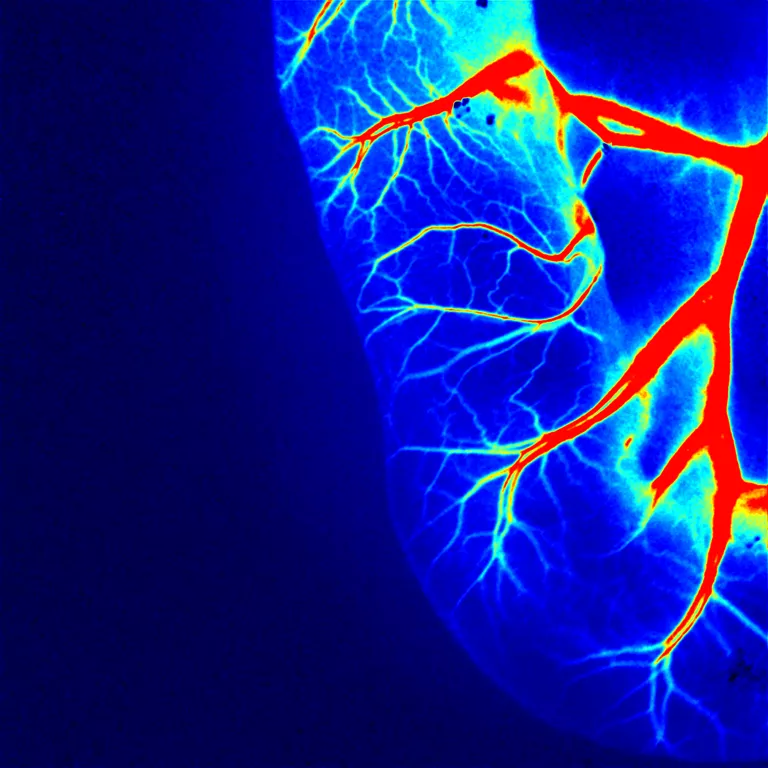

10、鸡胚尿囊膜微血管

▲13日龄鸡胚绒毛尿囊膜血管

在鸡胚胎发育过程中,CAM 是由尿囊的中胚层与绒毛膜的中胚层融合形成的。它是一种高度血管化、无神经支配的胚胎外膜,使其成为研究血管生成和肿瘤生长的理想基础模型。

对于血管再生研究,可以局部递送各种生物分子和药物并研究它们的血管生成效果。对于癌症模型,可以将各种类型的细胞移植到 CAM 中以促进肿瘤生长。这为研究许多不同的癌症肿瘤形成提供了一个相对简单的模型,并可进一步评估新的治疗药物和治疗方式。